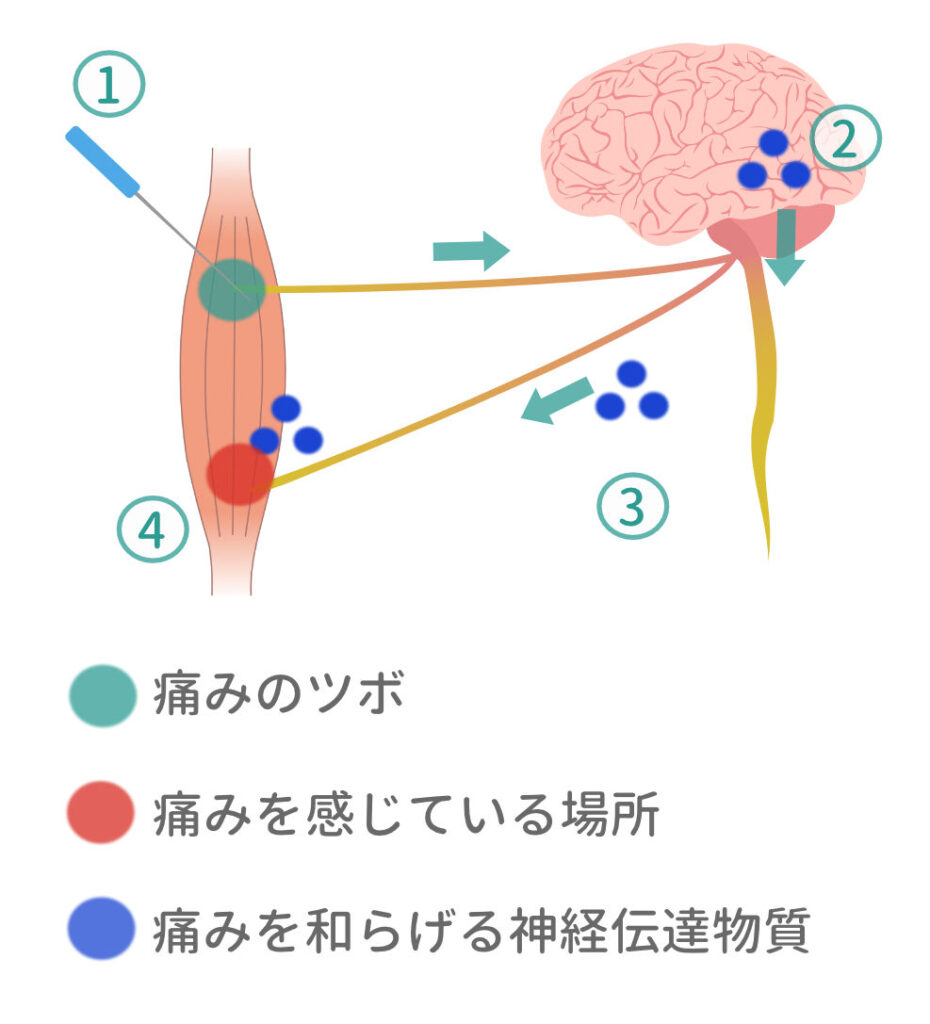

痛みがやわらぐ2つのメカニズム

1. 鍼灸のメカニズム

「痛みのツボ」を鍼で刺激します。

▼

鍼の刺激が脳に伝わると、痛みをやわらげる神経伝達物質が脳から分泌されやすくなります。

▼

寝起きにスッと立てるように

鍼を使い、ピンポイント(5~10ヵ所)に刺激をくわえます。※使い捨ての鍼を使用します。

※使い捨ての鍼を使用します。